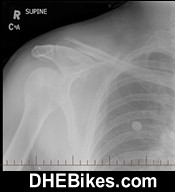

This is the pre-surgery x-ray of Downhill Dave's right shoulder. They should have operated at the hospital at the time of the accident but for some reason did not. 5 months after the accident the bones were still almost 2cm apart and would never fuse so surgery was required.

This crash happened during bike testing of a new all mountain bike from the Czech Republic where I was doing urban freeriding in Downtown Vancouver trying to break the dual suspension frame (to test its limits before I began distributing it). Unfortunately I did not know that the manufacturer had put light duty cross-country tubes in and when I landed about a 6 foot concrete staircase jump to flat the front tiire blew immediately, wrapped around the fork and slammed me into the concrete. OOOPSSS!!!